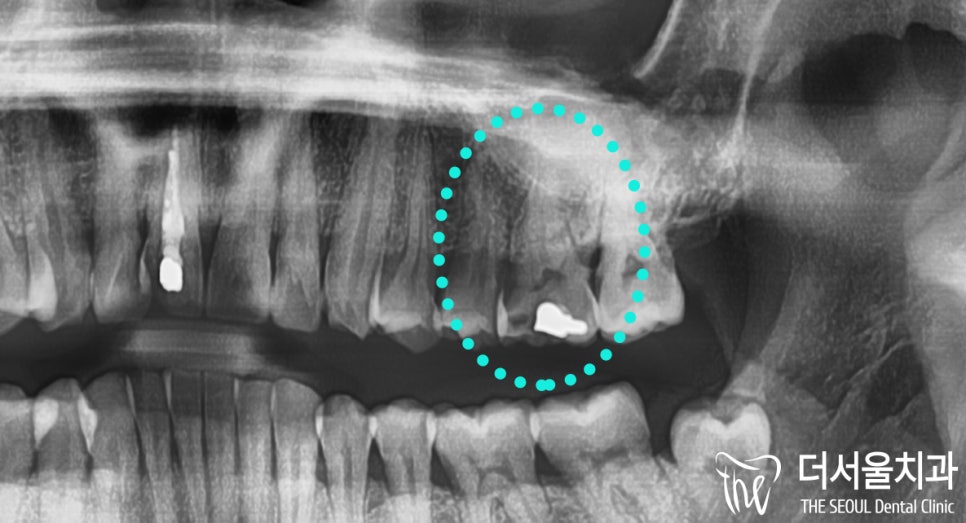

초진 사진을 확인한 결과,

이곳은 심한 충치가 나타나 있던 곳이였습니다.

파노라마에서 볼 수 있듯이

기존 보철 하방으로 검게 변해 있는 것을

한눈에 확인할 수 있지 않나요 ?

구강 내를 살펴보면

더욱 확연히 드러나는 것을 알 수 있습니다.

기존 보철 밑으로 심하게 썩어있는 충치와

치아 파절 의 범위를 확인할 수 있네요.